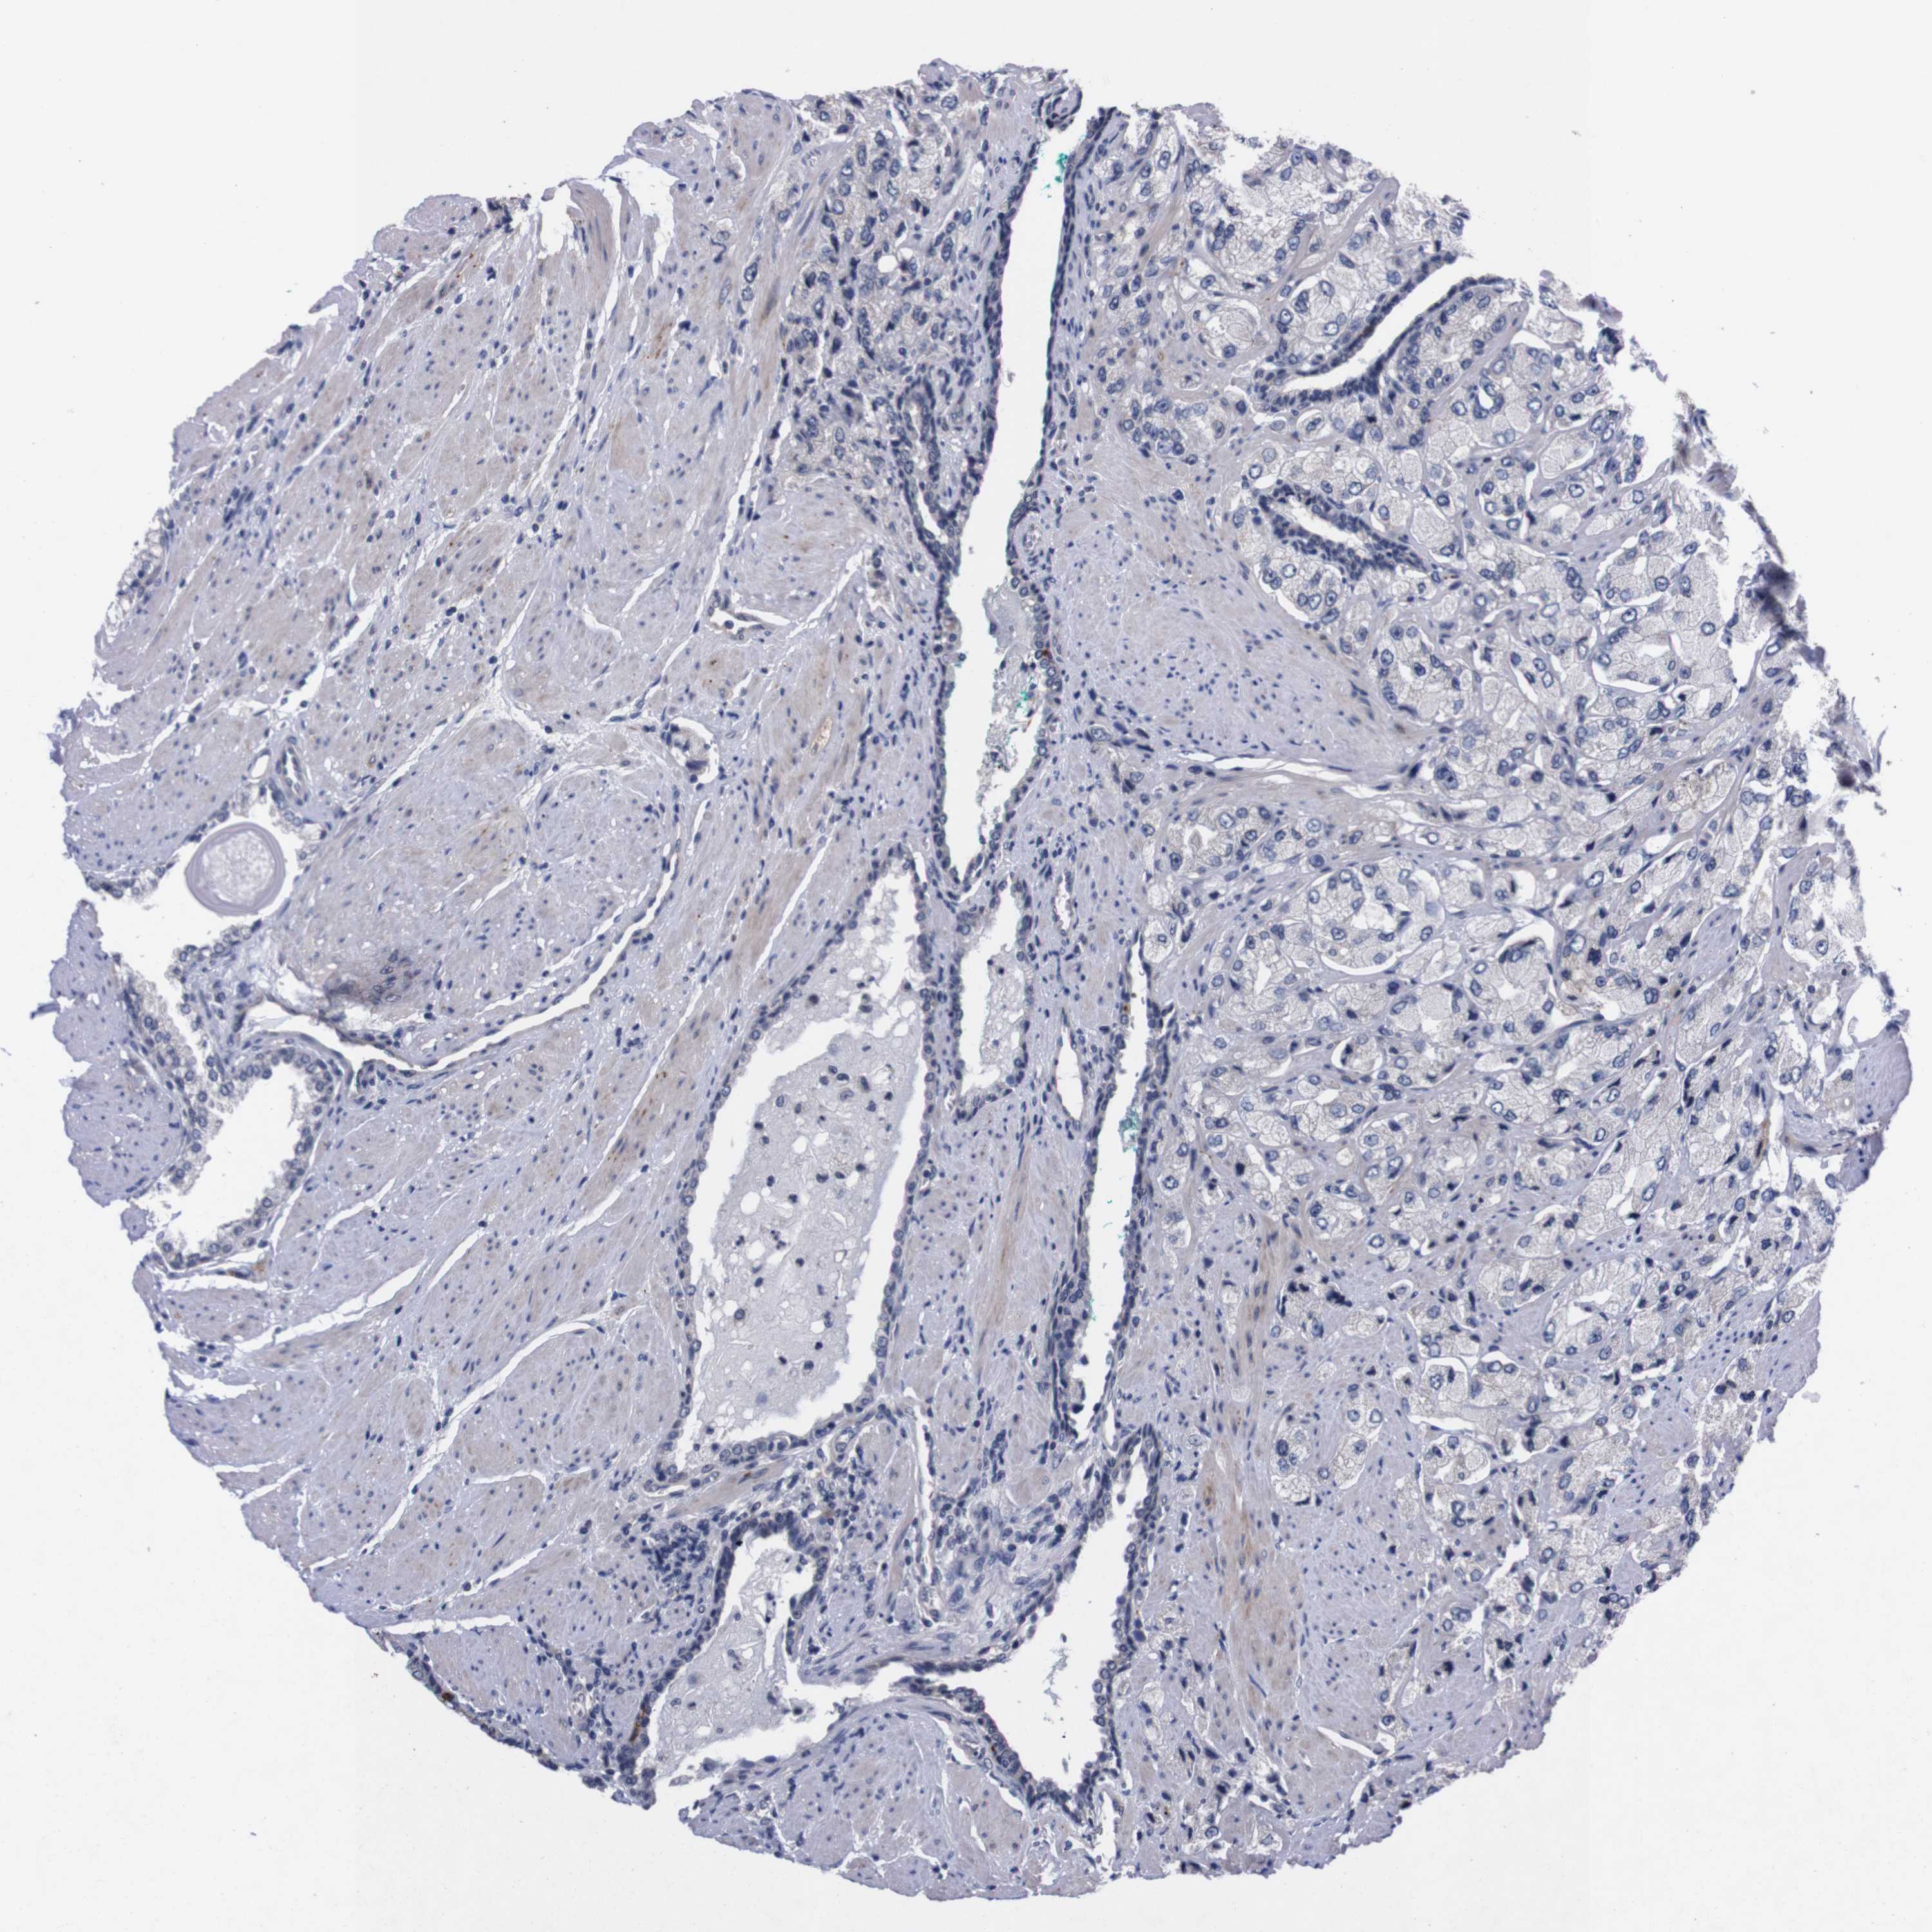

PROSTATE CANCER - Protein expressioni

A mouse-over function shows sample information and annotation data. Click on an image to view it in a full screen mode. Samples can be filtered based on level of antibody staining by selecting one or several of the following categories: high, medium, low and not detected. The assay and annotation is described here.

Note that samples used for immunohistochemistry by the Human Protein Atlas do not correspond to samples in the TCGA dataset.

Antibody stainingi

Antibody staining in the annotated cell types in the current human tissue is reported as not detected, low, medium, or high, based on conventional immunohistochemistry profiling in selected tissues. This score is based on the combination of the staining intensity and fraction of stained cells.

Each image is clickable and will lead to virtual microscopy that enables deeper exploration of all samples and also displays staining intensity scores, fraction scores and subcellular localization as well as patient and tissue information for each sample.

Antibody HPA006746

Antibody CAB009805

Staining

High

Medium

Low

Not detected

Intensity

Strong

Moderate

Weak

Negative

Quantity

>75%

75%-25%

<25%

None

Location

Nuclear

Cytoplasmic/membranous

Cytoplasmic/membranous,nuclear

Adenocarcinoma, Low grade

Adenocarcinoma, High grade